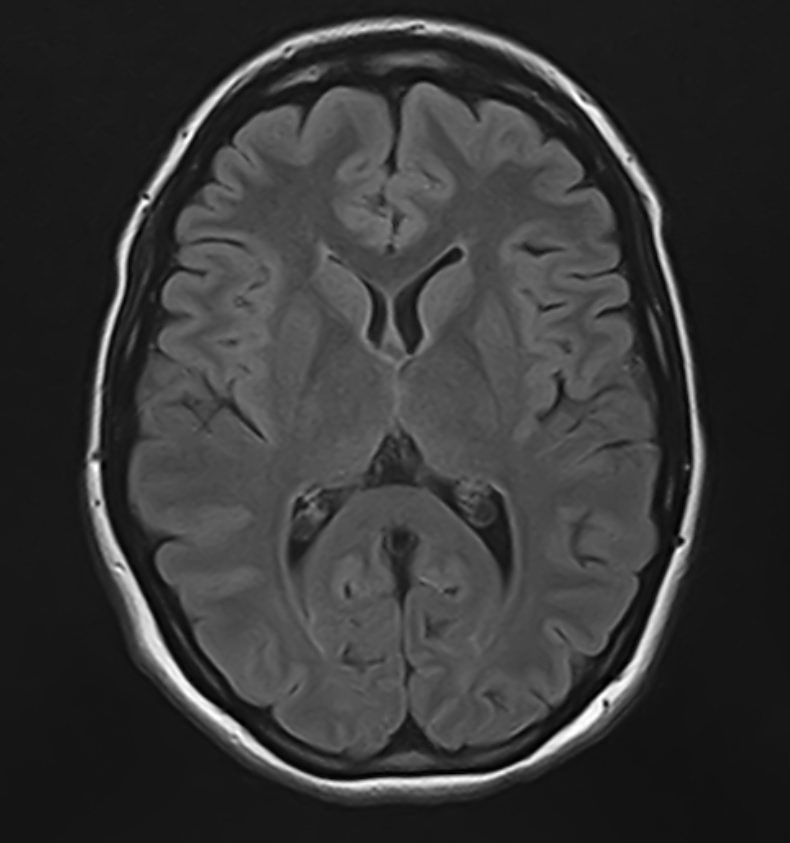

К центральной нервной системе организма относится головной мозг, расположенный в полости черепа, и спинной мозг, проходящий в спинномозговом канале позвоночного столба. В головном мозге находятся высшие центры управления всем организмом, спинной мозг имеет двусторонние связи с ними, то есть является проводником импульсов от периферии к головном мозгу и обратно.

Патология ЦНС может проявляться многообразной неврологической симптоматикой, в зависимости от уровня поражения. Причинами ее появления могут быть травматические повреждения, проникновение инфекции, демиелинизирующие и дегенеративные заболевания, сосудистая патология, опухолевые процессы.

Для диагностики заболеваний ЦНС в клинике «Доступная медицина» проводится комплексное обследование МРТ ЦНС (центральной нервной системы). Клиника укомплектована высокотехнологичным оборудованием, в частности, новейшим 32-канальным высокопольным томографом TOSHIBA VANTAGE TITAN 1,5 Тесла с высокой разрешающей способностью для точной диагностики заболеваний центральной нервной системы.

Комплексное обследование ЦНС выполняется как в стандартном режиме, когда не применяется использование контраста, так и с контрастным усилением. Для более точной диагностики некоторых патологий головного и спинного мозга внутривенно вводится контрастное вещество. С помощью контраста можно обнаружить опухолевые образования размером от 1 мм, демиелинизирующие процессы, дегенеративно-дистрофические заболевания, воспалительные процессы, сосудистую патологию.

МРТ головного и / или спинного мозга показано при диагностике повреждений, структурных отклонений или других состояний, таких как: